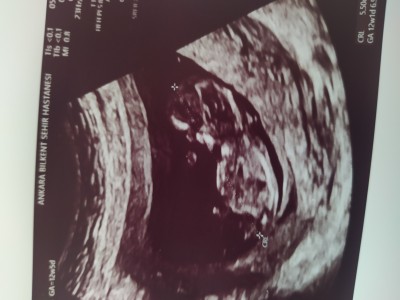

Bize de tahmin yapar mısınız?

Gebelik haftası 12+5

Kıza benziyor Rabbim sağlıkla nasip etsin